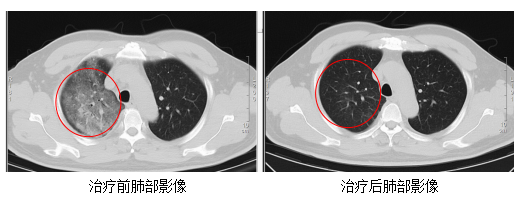

发热门诊医生详细询问顾先生的既往病史,并为其进行细致的体格检查。胸部CT结果显示,顾先生的双肺存在大面积的炎症病变。

在感染科医护团队的精心治疗与细致护理下,顾先生的发热、咳嗽、胸闷等症状逐渐缓解。复查的CT结果显示,肺部炎症情况得到了明显的改善。目前,顾先生已经顺利康复出院。